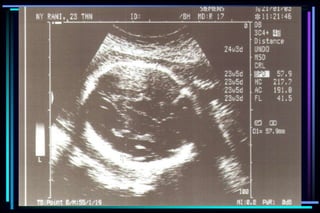

2nd and 3rd trimester

 Fetal number

 Presentation

 Fetal heart motion

 Placental location

 Amniotic fluid volume

 Gestational age

 Survey of fetal anatomy

 Evaluation for maternal

pelvic mass

Accuracy of ultrasound measurement for

different gestational groups

Ultrasound parameter Accuracy

 Gestational sac diameter + 7 days

 Crown Rump Length + 3-5 days

 BPD second trimester + 1 to 1.5 weeks

 BPD third trimester + 2 to 4 weeks

 FL second trimester + 1 to 1.5 weeks

 FL third trimester + 3 to 3.5 weeks

 Multiple parameter (2nd trimester) + 1.5 weeks

 Multiple parameter (3rd trimester) + 2.5 weeks